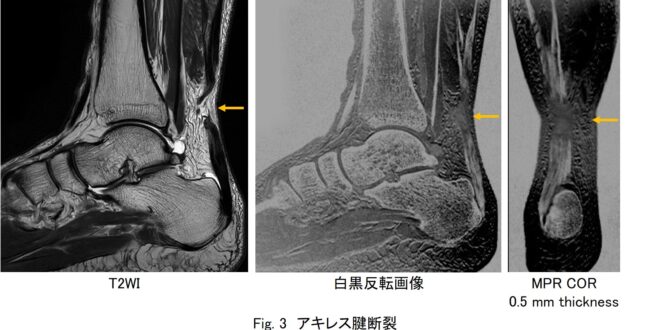

• シングルエコーによるアキレス腱描出シーケンス | MRIfan.net